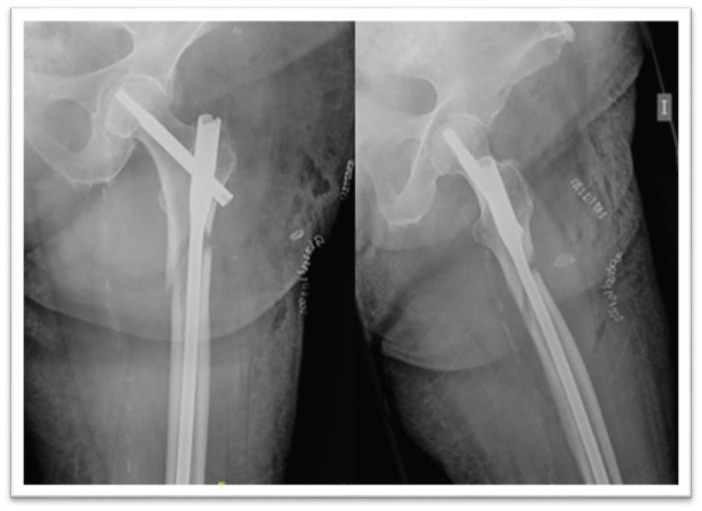

Objectives: Treatment of subtrochanteric fractures of the proximal femur may be challenging due to their anatomical and biomechanical features. Intramedullary nails are the most frequently used devices, although there is no consensus concerning their optimal length. The aim of this study is to compare the functional and radiological outcomes of the fragility subtrochanteric fractures treated with short versus long cephalomedullary nails.

Methods: A retrospective cohort study was performed including all over-65-year-old patients that underwent surgery with a cephalomedullary nail between January 2013 to December 2020 due to a subtrochanteric fracture. The primary outcome was the presence of mechanical complications (cut out, cut in, varus consolidation, nonunion and nail breakage). Accuracy of the reduction, distance from the fracture line to most proximal distal screw, operative time and Palmer Mobility score were also analyzed.

Results: Ninety-five patients were included. There were not significant differences in complication rate, Parker mobility score nor quality of reduction between both cohorts. Patients with a good radiological reduction presented no complications, those with an acceptable reduction presented a complication rate of 35.5% and it raised to 53.3% in poorly reduced ones (P=0.002). The complication rate was higher in the <5cm distance group (58.33%) than in the >5cm distance group (22.64%) (P=0.014).

Conclusion: Anatomical reduction may be the key factor in the management of subtrochanteric fractures, in order to avoid complications. The chosen device working length should also be taken into account to treat these challenging injuries.